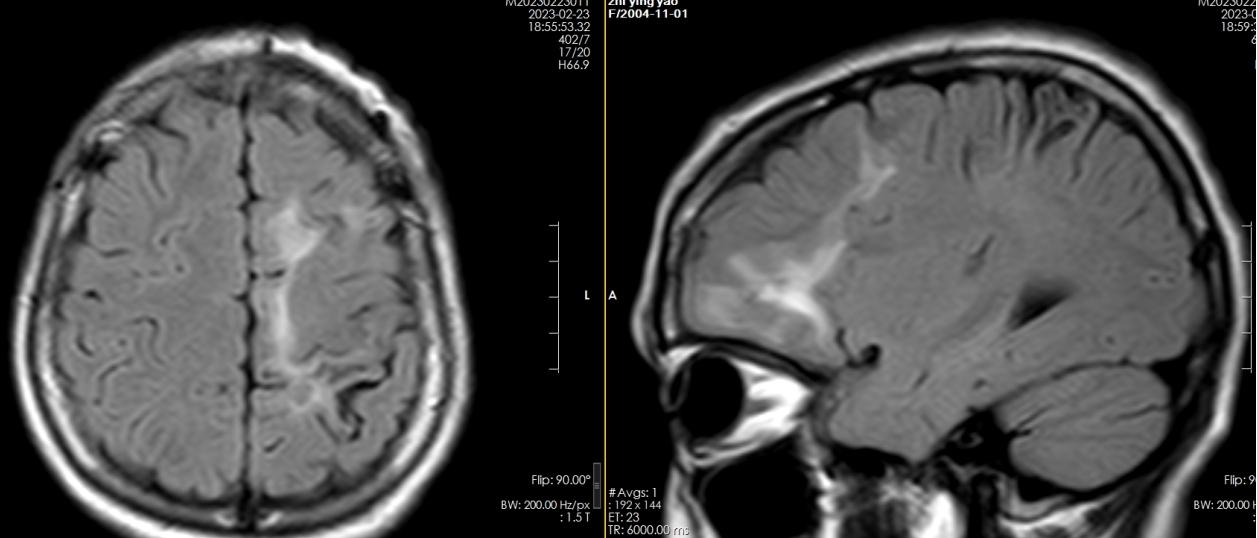

该院神经外八科(癫痫外科)副主任陈俊喜接诊患者后,发现患者左侧额叶存在多发病变,且两次发作症状不尽相同,怀疑是寄生虫感染。进一步检查结果提示:裂头蚴IgG抗体阳性;视频脑电图显示:左侧额顶叶多发放电。

“多发脑软化灶实为虫体在颅内爬行产生的损伤。”陈俊喜补充介绍,“患者癫痫发作的根源在于寄生虫对大脑的炎性刺激,造成大脑异常放电。”

通过间隔2周的观察,专家团队最终精准定位到寄生虫位于患者左侧额叶前部,并在三维脑上描记了虫体位置。2月21日,陈俊喜带领团队为患者实施寄生虫抓取及肉芽肿切除术,顺利“活捉”一条长约11厘米的裂头蚴,连同“虫窝”也一并切除了。